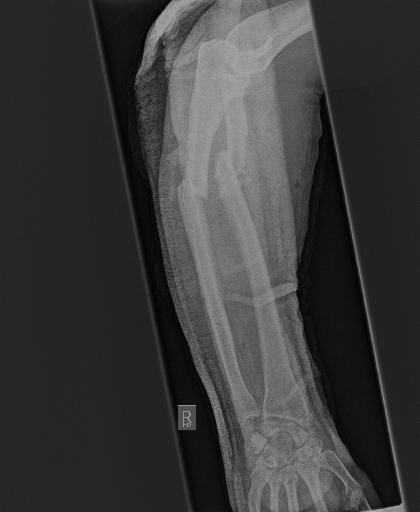

Bone 이미지 데이터 350장 중 Fracture 이미지 50장, Implant 이미지 50장, Bone 이미지 50장을 선별했다.

train과 val은 라벨링을 해야한다. 어제 라벨링을 했었지만, Fracture는 좀 넓게 잡고, Implant는 최대한 여러개로 쪼개는 느낌으로 라벨링을 다시했다.